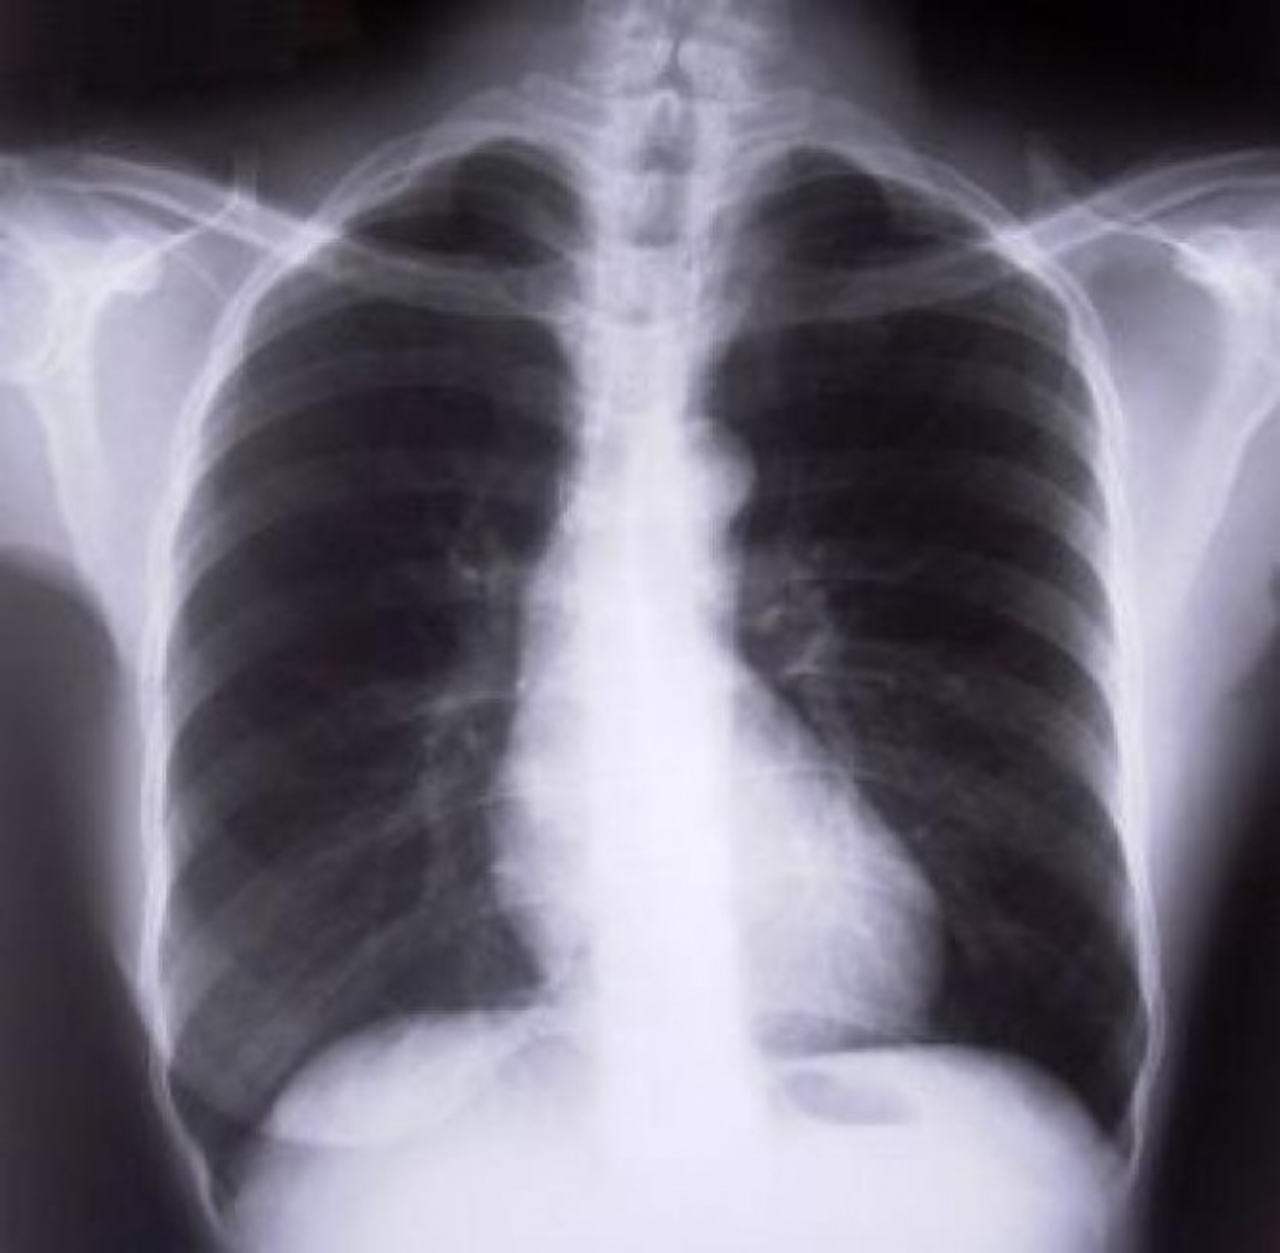

- Przede wszystkim powinien unikać wziewnych substancji szkodliwych. Po pierwsze, jeśli pali, to jak najszybciej powinien pożegnać się z nałogiem. Jeżeli wypala jakąkolwiek biomasę, to też unikać tego. Oprócz tego wykonać badania, prześwietlenie klatki piersiowej, spirometrię, no i w przypadku diagnozy i rozpoznania Przewlekłej Obturacyjnej Choroby Płuc pacjent powinien podjąć niezwłocznie leczenie – radzi lek. Med. Marzena Renflejsz